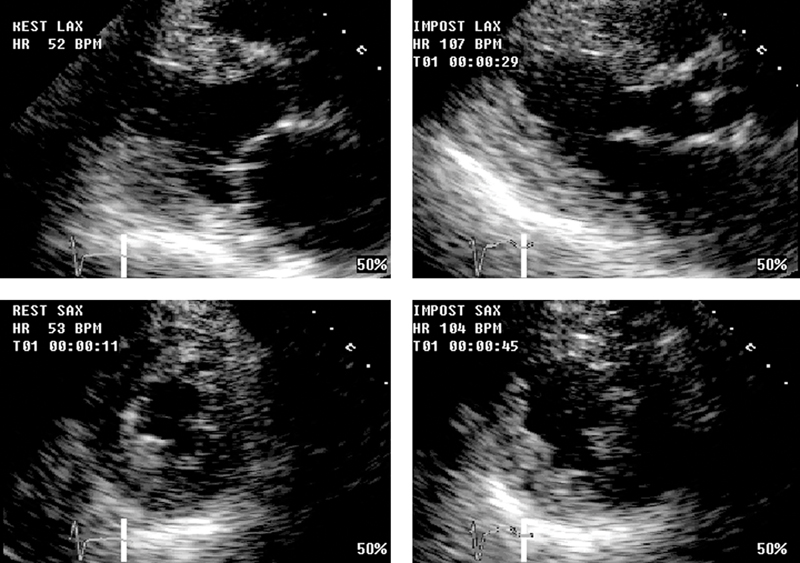

فحوصات تشخيصية لبعض امراض القلب والشرايين التاجية